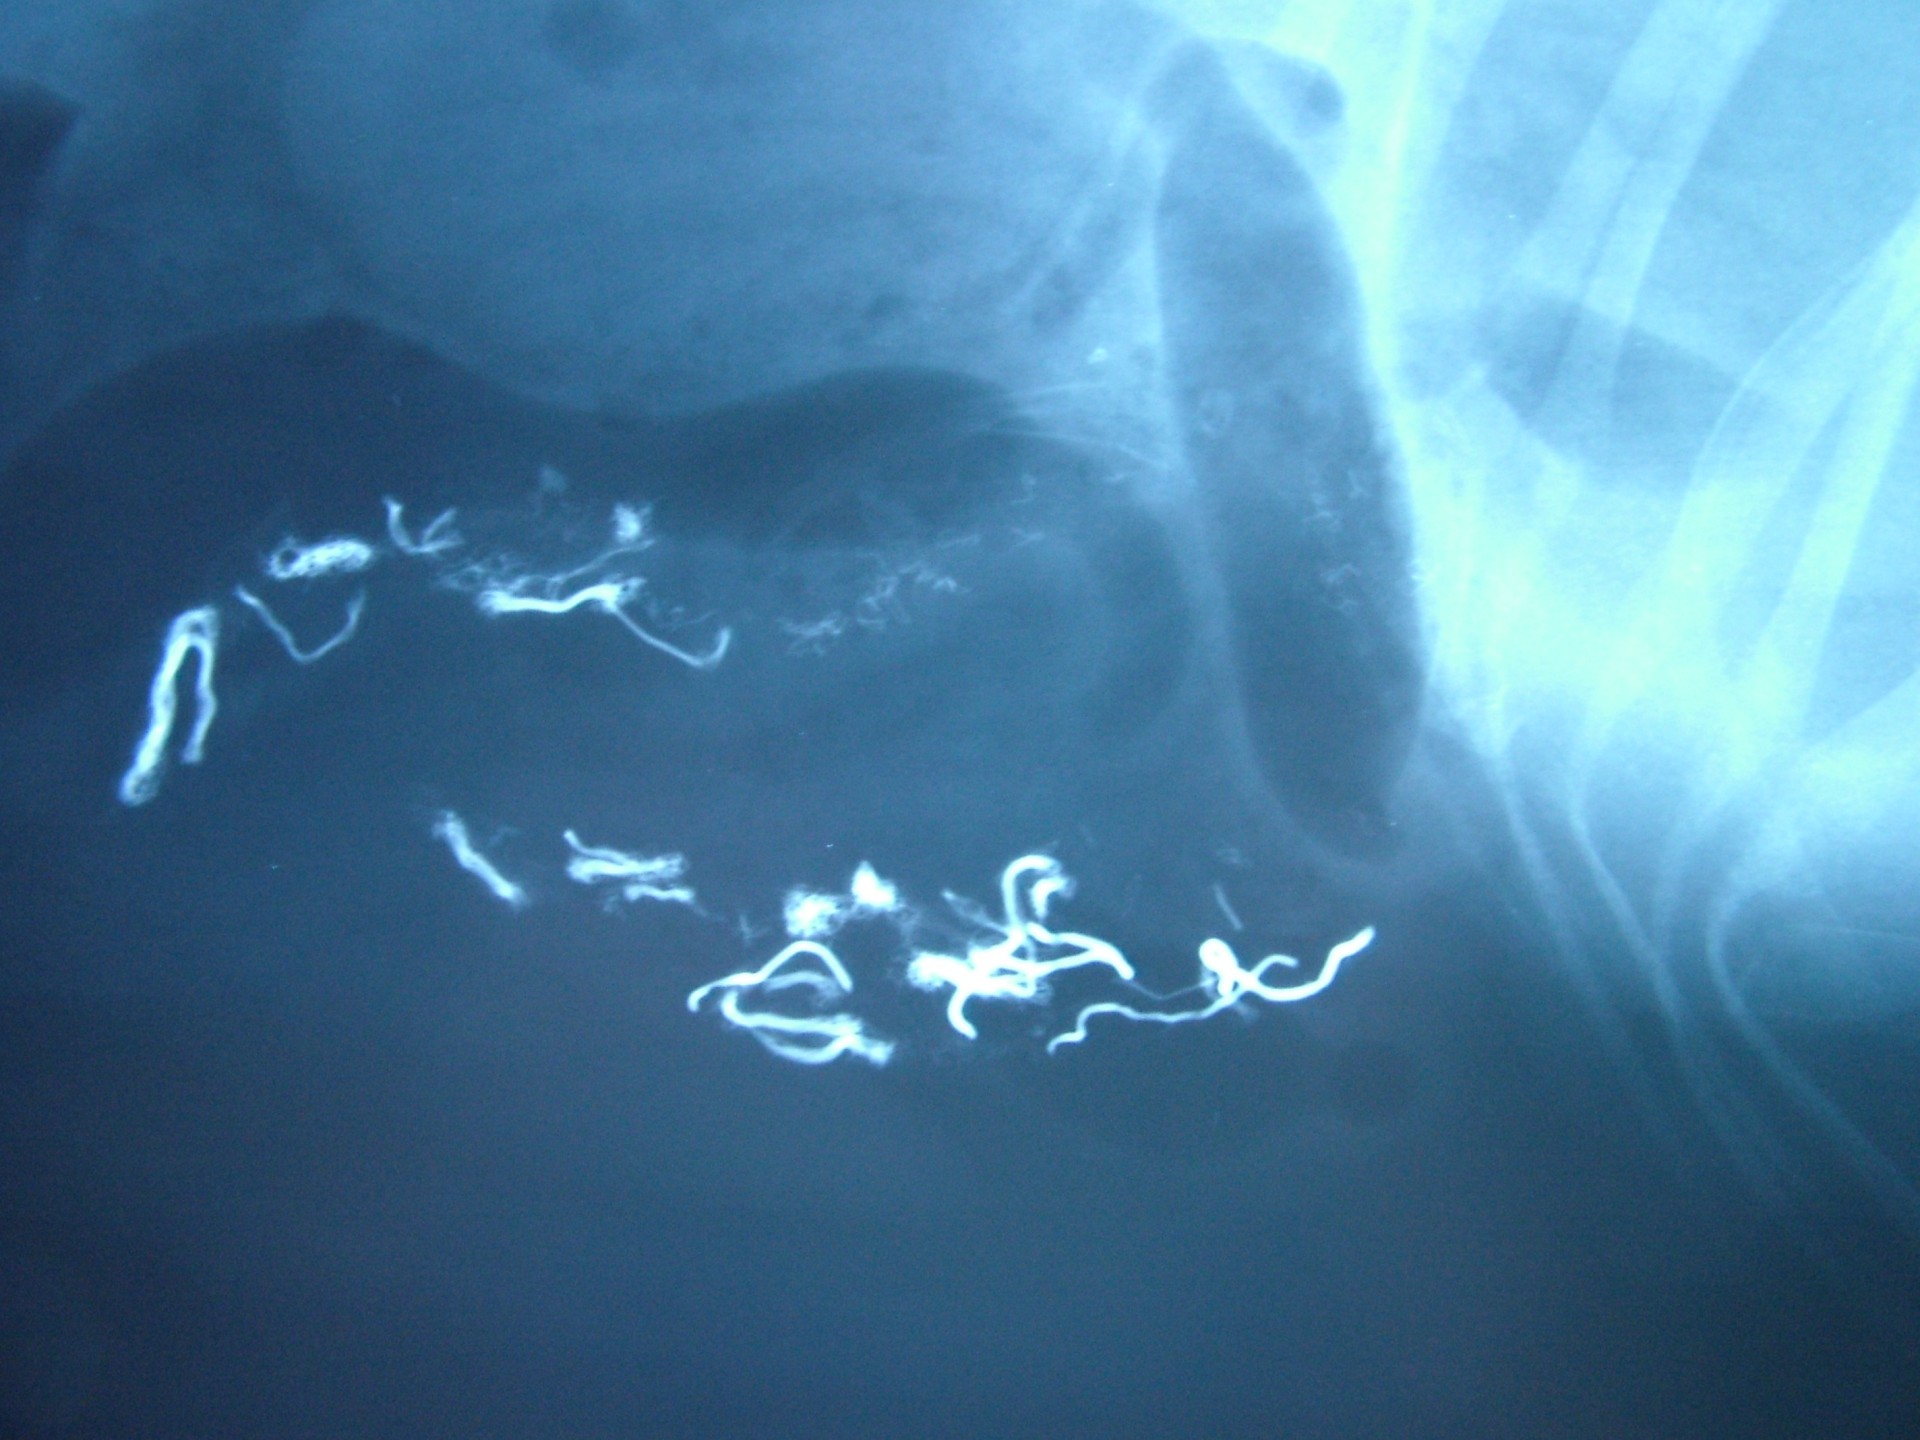

• A lineáris idegentest okozta ileus nem tényleges értelemben vett bélelzáródás, mert ebben az esetben az idegentest cérna, fonal vagy más fonalszerű képlet, mely a bélrendszerbe kerülve a bélfodor mentén, rozettaszerűen felfűzi a bélcsatorna egy részét, így akadályozva meg a táplálék tovahaladását.

A különféle bélelzáródások diagnosztikája során a kórelőzmény (pl.: játék lenyelése) és a klinikai tünetek (hányás, a has feszítése, tapintható idegentest a hasüregben stb.) mellett kiegészítő vizsgálatként RTG vizsgálat és a hasüreg ultrahangos vizsgálata jöhet szóba. A bél elzáródását okozó képletek az esetek döntő többségében nem adnak röntgen árnyékot, ezért un.: röntgen kontrasztanyagot etetünk az állattal és többszöri röntgenfelvétel készítésével figyeljük a tovahaladását.

Abban az esetben, ha a kontraszt anyag elakad, az ileus diagnózisa nagy biztonsággal kimondható. Ultrahangos vizsgálattal a bélelzáródás előtti területen felhalmozódó béltartalom un.: inga-mozgása is egyértelműen bélelzáródásra utaló diagnosztikai jel.